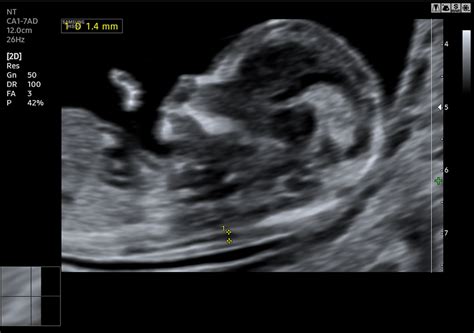

Általános gyakorlat ugyanis, hogy amennyiben a 18-20. héten elvégzett genetikai ultrahangon a szakorvos valamilyen rendellenességet talál a magzat szívfejlődése kapcsán, esetleg magas rizikófaktort állapít meg, akkor idejekorán szükség lehet egy magzati szívultrahang-vizsgálatra.

A korszerű orvostudománynak és a modern felszereléseknek köszönhetően már az anyaméhen belül elvégezhető egy ilyen vizsgálat, amivel idejekorán kiszűrhetők az esetleges szívproblémák.

A szívultrahang vizsgálat vagy más néven echokardiográfiás vizsgálat során egyszerű ultrahangos technológiával tudják megvizsgálni a magzat szívét úgy, hogy a szakorvos egy számítógép képernyőjén minden apró részletet szemügyre tudjon venni.

Készíthető úgynevezett Doppler-teszt is, ami nagy mennyiségben bocsát ki magas frekvenciájú hullámokat, melyek egyrészt visszaverődnek, másrészt pedig elnyelődnek a szervezetben, de alapvetően nem károsak a magzatra.

Bizonyos esetekben pedig életmentő lehet, hiszen a segítségével nemcsak képet kap a kardiológus magáról a szívről, hanem a benne áramló vér sebességét és irányát egyaránt meg tudja mérni.

A legtöbbször mindkét tesztre szükség van ahhoz, hogy a gyermekkardiológus minden esetleges problémát fel tudjon tárni, illetve átfogó képet kaphasson a gyermek szívéről, annak anatómiájáról és funkcionális állapotáról egyaránt.